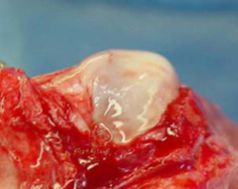

La luxation de la rotule résulte occasionnellement d’une lésion traumatique du genou, provoquant une boiterie sévère soudaine du membre. Cependant, la cause précise reste incertaine chez la majorité des chiens mais est probablement multifactorielle. La rainure fémorale dans laquelle se trouve normalement la rotule est généralement peu profonde (Figure 2a, Figure 2b) ou absente chez les chiens présentant une luxation patellaire non traumatique. Le diagnostic précoce de la maladie bilatérale en l’absence de traumatisme et la prédisposition de la race soutiennent le concept que la luxation patellaire résulte d’un désalignement congénital ou développemental de l’ensemble du mécanisme de l’extenseur. La luxation patellaire développementale n’est donc plus considérée comme une maladie isolée du genou, mais plutôt comme une conséquence d’une anomalie squelettique complexe affectant l’alignement global du membre, incluant:

Fig. 2b Vue peropératoire de la même rainure fémorale avant correction